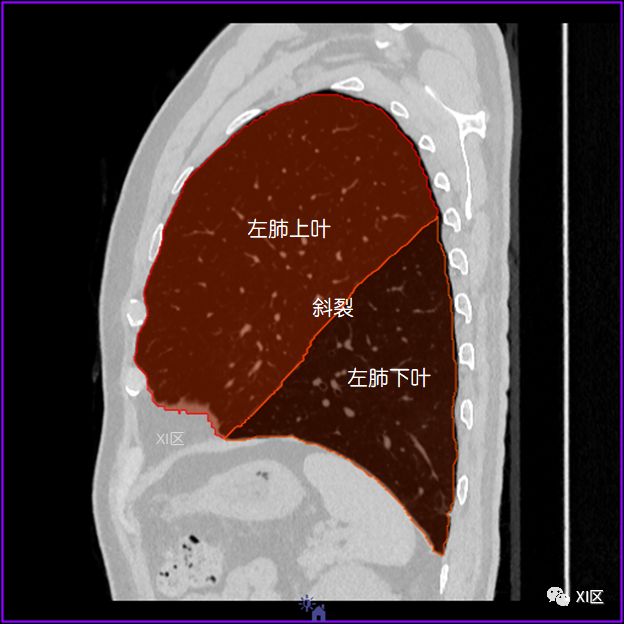

左肺借斜裂成上、下两叶;右肺借斜裂和水平裂成上、中和下叶三叶。

矢状位

肺表面重建显示叶间裂和肺的分叶

透视图显示肺的叶间裂和肺的分叶

肺的分叶